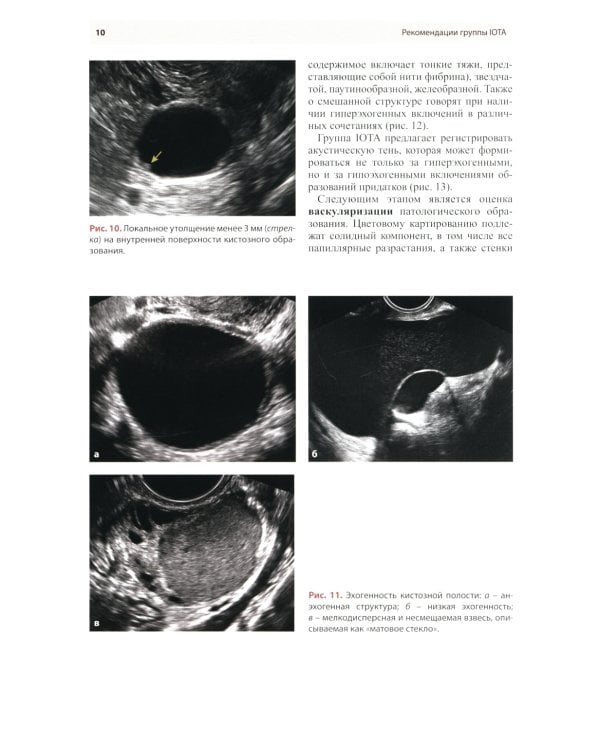

Методические рекомендации по стандартизации ультразвукового исследования с целью своевременной диагностики опухолевого процесса. Книга также включает вопросы дифференциальной диагностики физиологических изменений яичников, опухолевидных и опухолевых заболеваний и маршрутизации пациенток. Утверждено в качестве методических рекомендаций для проведения циклов первичной переподготовки врачей по ультразвуковой диагностике, тематического усовершенствования «Ультразвуковая диагностика в гинекологии», общего усовершенствования, ординаторов и аспирантов, проходящих обучение по направлению «Ультразвуковая диагностика, акушерство и гинекология».| Издательство | МЕДпресс-информ |